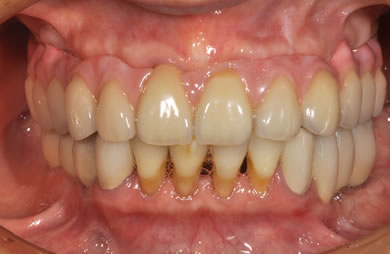

骨再生スピードインプラント治療+AGC連結セラミック治療

| 主訴 | 他院で骨の量が足りずインプラントは難しいと言われ、入れ歯を使用していたが、やはりインプラント治療をうけたい。 | ||||||||||||||||||||||||||||||||

| 治療方針 | 上顎の歯周組織がかなり侵襲されているため、ソケットリフト法にて骨を回復させ、機能的回復だけでなく審美的回復も行うためにAGCハイブリッド連結ブリッジにて補綴処置を行う。 | ||||||||||||||||||||||||||||||||

| 治療内容 | インプラント12本(ソケットリフト+抜歯即日スピードインプラント)、ハイブリッドセラミック8本、AGCハイブリッドセラミック連結ブリッジ1装置、テンポラリーインプラント2本、遊離歯肉移植術 | ||||||||||||||||||||||||||||||||